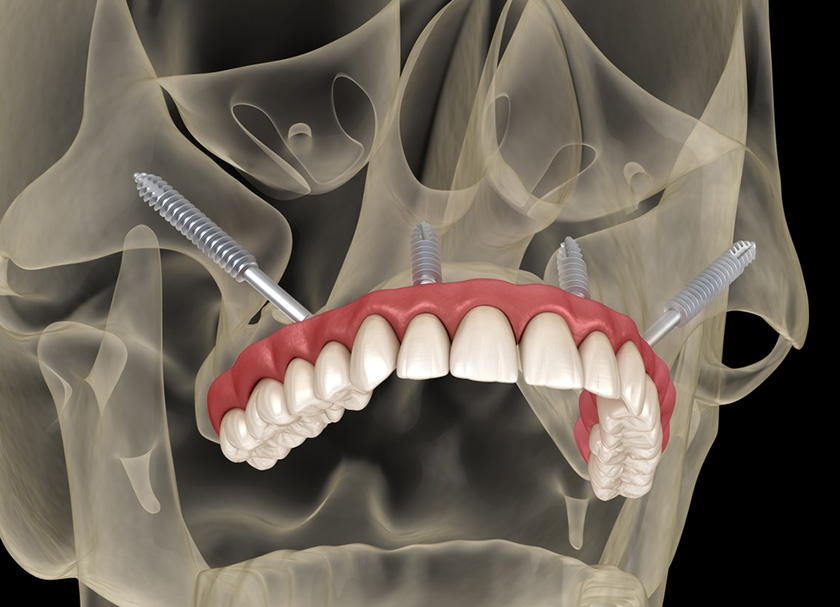

Zygomatic implants can replace upper teeth.

These implants are intended to replace the teeth in the upper jaw and can replace an entire arch of missing teeth or severely damaged or decayed teeth. They are an ideal choice for patients who cannot be considered for traditional dental implants due to a lack of bone mass.

Zygomatic implants are called that way because they are implanted into the zygomatic bone, commonly known as the cheekbone. Compared to the maxillary bone, the cheekbone is much denser and provides a more solid anchor point for the implant.

- They can be used on patients with poor maxillary bone quality or lacking bone mass. It is because they are anchored in the zygomatic bone, not the maxillary bone. Unlike jawbones, zygomatic bones do not lose bone mass due to missing teeth or periodontal diseases.

- When our dentists place these implants, they are angled into the zygomatic bone. The dense composition of the bone, along with the angulation of the implant, allows a dental prosthetic to be immediately loaded onto the implants during the surgery. It means you won’t go without teeth while your dental implants heal.